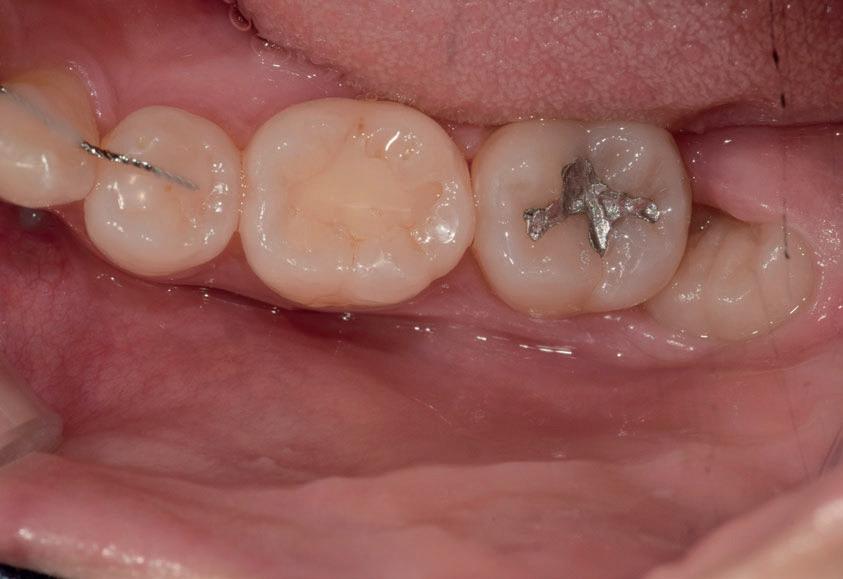

Questo è un paziente di 22 anni ed essendo un amico, ho potuto ben documentare il caso con il suo consenso: il suo dente del giudizio inferiore sinistro è stato estratto utilizzando il manipolo dritto. Figg. 143-149

Figg. 143-149 - Caso 1, paziente di 22 anni: tecnica di estrazione con divisione orizzontale utilizzando il manipolo dritto. Fig. 143 Fig. 144 Fig. 145 Fig. 146 Fig. 147 Fig. 148 Fig. 149